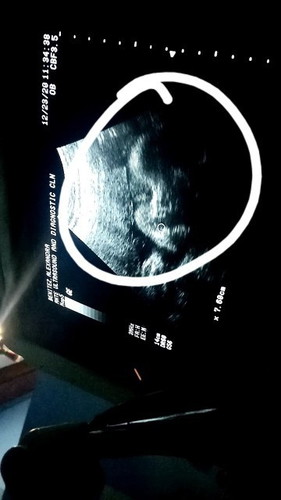

HYDROCEPHALUS

Question lang po, ano po ba mga sintomas ng hydrocephalus? ito po yung huling ultrasound ko. parang ang laki po ng ulo ni baby, normal lang ba yung laki ng ulo niya? natatakot po kasi ako baka mamaya may komplikasyon si baby ko